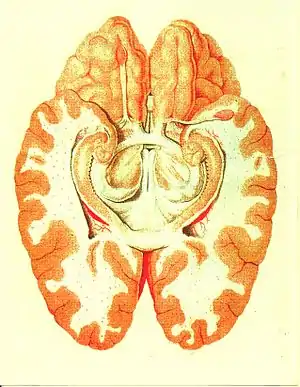

Cross section of the human brain showing parts of the limbic system from below. Traité d'Anatomie et de Physiologie (1786) | |